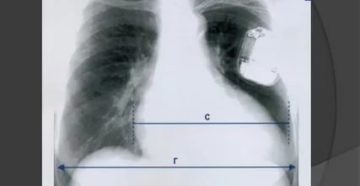

Рентгенография грудной клетки: показания к проведению диагностики Рентген грудной клетки — частая диагностическая процедура, которая…